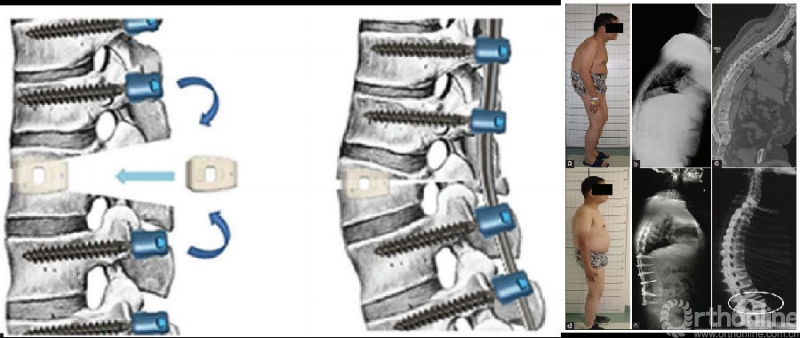

Cage

Hu等提出在PSO治疗AS胸腰椎后凸畸形过程中,截骨间隙内放置cage可有效降低ST的发生风险(cage组ST发生率4.7%vs.非cage组ST发生率30.4%,χ2=10.020,P=0.002)。cage置入截骨间隙后即刻发生下沉入头端和尾端的椎体松质骨内,可作为截骨间隙闭合过程中的铰链,能够有效限制头尾端椎体的移位,降低前皮质骨折断裂后的ST发生风险。

复位导向器

钱邦平等设计复位导向器应用于PSO矫正AS胸腰椎后凸畸形,构件包括一个弧形滑轨和两个支杆。术者在截骨面闭合过程中,握住两个操作手柄,以保证复位过程中复位装置的整体稳定性。

临床应用发现27例AS胸腰椎后凸畸形患者,术中应用复位导向器械均能有效预防截骨椎脱位的发生。复位导向器的使用指征主要包括AS胸腰椎单平面后凸畸形患者,对合并冠状面侧凸畸形及假关节形成患者不宜使用。